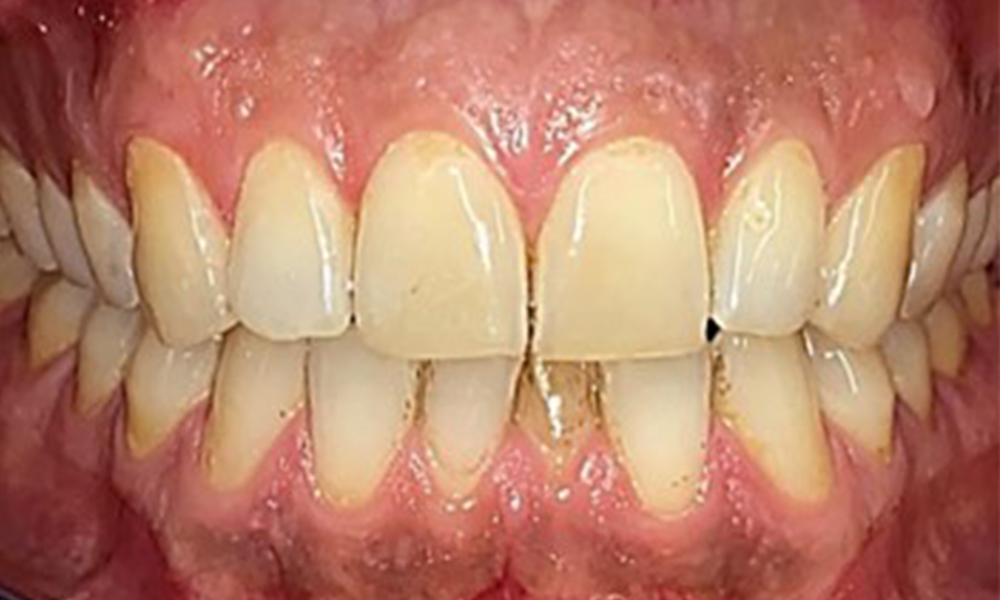

Дентални резултати

Пациентът има пълно съзъбие с общо 28 зъба. Налице са забележими ерозии и атриции. (Фиг. 4, Фиг. 5). Поради бруксизъм пациентът е носил шина с коригиран блок на захапката през нощта в продължение на много години. Ерозиите са причинени от продължителна консумация на изотонични напитки. Не сe наблюдава загуба на пародонтална кост или активни кариозни лезии.